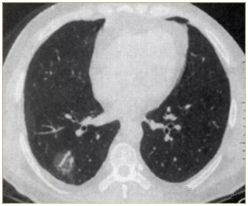

肺部小結(jié)節(jié)通常是指影像檢查(X線或者CT)中發(fā)現(xiàn)的直徑≤2cm的類圓形病灶,≤3cm的稱為結(jié)節(jié),>3cm的稱為腫塊。

也有學(xué)者認(rèn)為,分得太細(xì)并無意義,例如2.2cm的結(jié)節(jié)與1.9cm的小結(jié)節(jié),臨床上并沒有本質(zhì)的區(qū)別。在這里我們統(tǒng)一把≤3cm的結(jié)節(jié)統(tǒng)稱為肺部小結(jié)節(jié),在肺部小結(jié)節(jié)中,60%—70%為良性結(jié)節(jié),30%—40%的結(jié)節(jié)方為惡性結(jié)節(jié),所以,發(fā)現(xiàn)肺部小結(jié)節(jié)切勿驚慌。

結(jié)節(jié)的大、小與良、惡性有一定的相關(guān)性,當(dāng)肺部結(jié)節(jié)>3cm的病灶多為惡性,而微小的結(jié)節(jié),良性的可能性居多。

我們常看到的影像學(xué)描述中的“磨玻璃結(jié)節(jié)(GGO)”,其中一部分是非典型腺瘤樣增生(AAH)或原位腺癌(AIS),結(jié)節(jié)內(nèi)部的實(shí)變與生長速度的加快(范圍變大)常意味病變性質(zhì)的轉(zhuǎn)變,可以逐步演變?yōu)槲⒔櫹侔∕IS)、浸潤性腺癌(IAC)。

肺部小結(jié)節(jié)對患者的危害,有時(shí)心理還大于生理。其實(shí),不用擔(dān)心的,因?yàn)楹芏嗖⒉灰欢ㄊ前?/span>